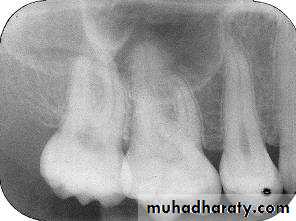

The molar-bitewing. A, Film placement. B, Resultant radiograph.

A

B